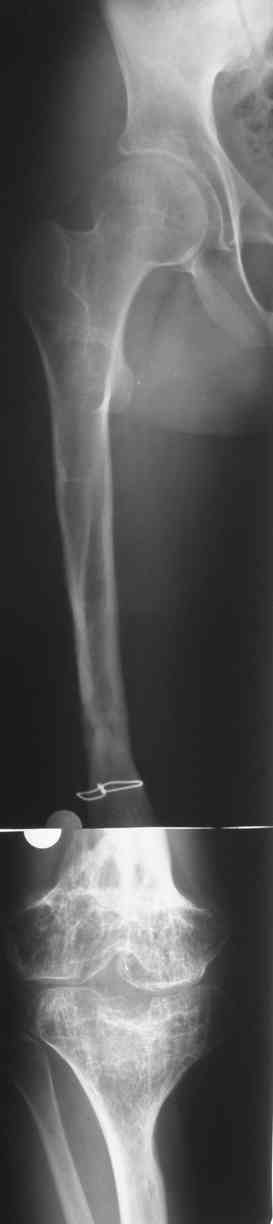

Re: Фиброзная дисплазия бедра, укорочение 12 см.

Спасибо за ответы. Это рентгенограммы пациента до и после последнего удлинения бедра